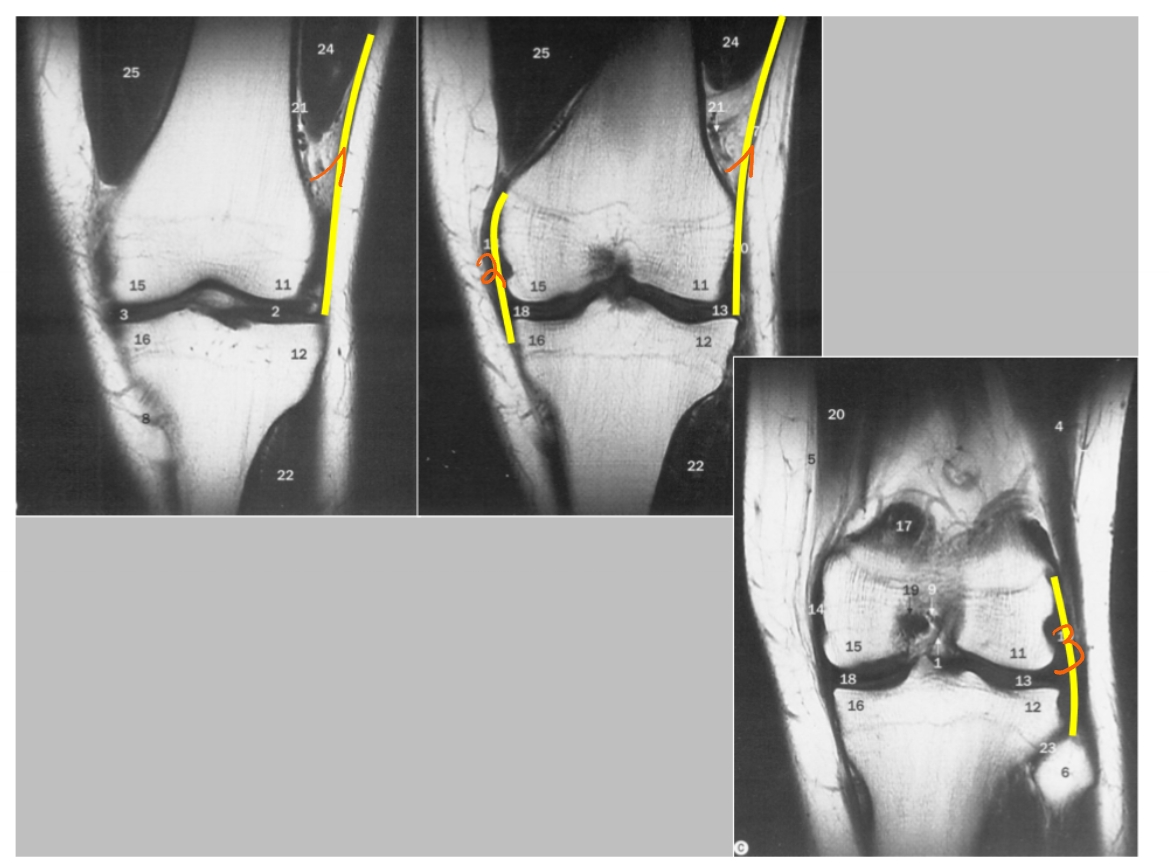

patella

epicondylus lateralis

epicondylus medialis

condylus lateralis femoris

condylus medialis femoris

condylus lateralis tibiae

condylus medialis tibiae

spina intercondylaris

daarop hechten de kruisbanden aan

area intercondylaris

caput fibula

→ rechterknie

femur

→ linker knie (MR): dwarse doorsnede

→ linker knie (MR): coronale doorsnede